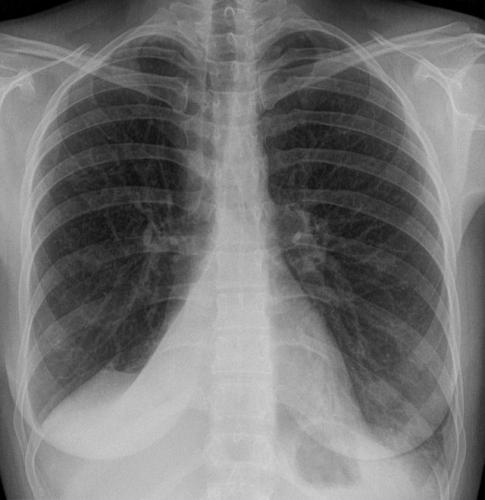

Помимо опроса и объективного осмотра, включающего перкуссию и аускультацию грудной клетки, проводят рентгенологическое исследование в двух положениях тела (в 2-х проекциях). Это основной метод обнаружения ателектазов легких.

На рентгеновских снимках выявляют следующие признаки, указывающие на спадение легочной ткани:

Однородное затемнение в области поражения. Размеры тени зависят от вида ателектаза: при долевом выявляется обширное затемнение, при сегментарном — в виде клина или треугольника, расположенного вершиной к корню легкого, дольковые ателектазы множественные и похожи на очаговую пневмонию. Дистензионный ателектаз расположен низко, около диафрагмы, имеет небольшие размеры и вид поперечных полос или темных дисков. Смещение органов: при компрессионном ателектазе смещение наблюдается в здоровую сторону, так как на стороне поражения давление больше, при обтурационном, наоборот – смещение будет в сторону ателектаза, так как на стороне поражения нарастает притягивающее отрицательное давление. Подъем купола диафрагмы – это видно по расположению печени.